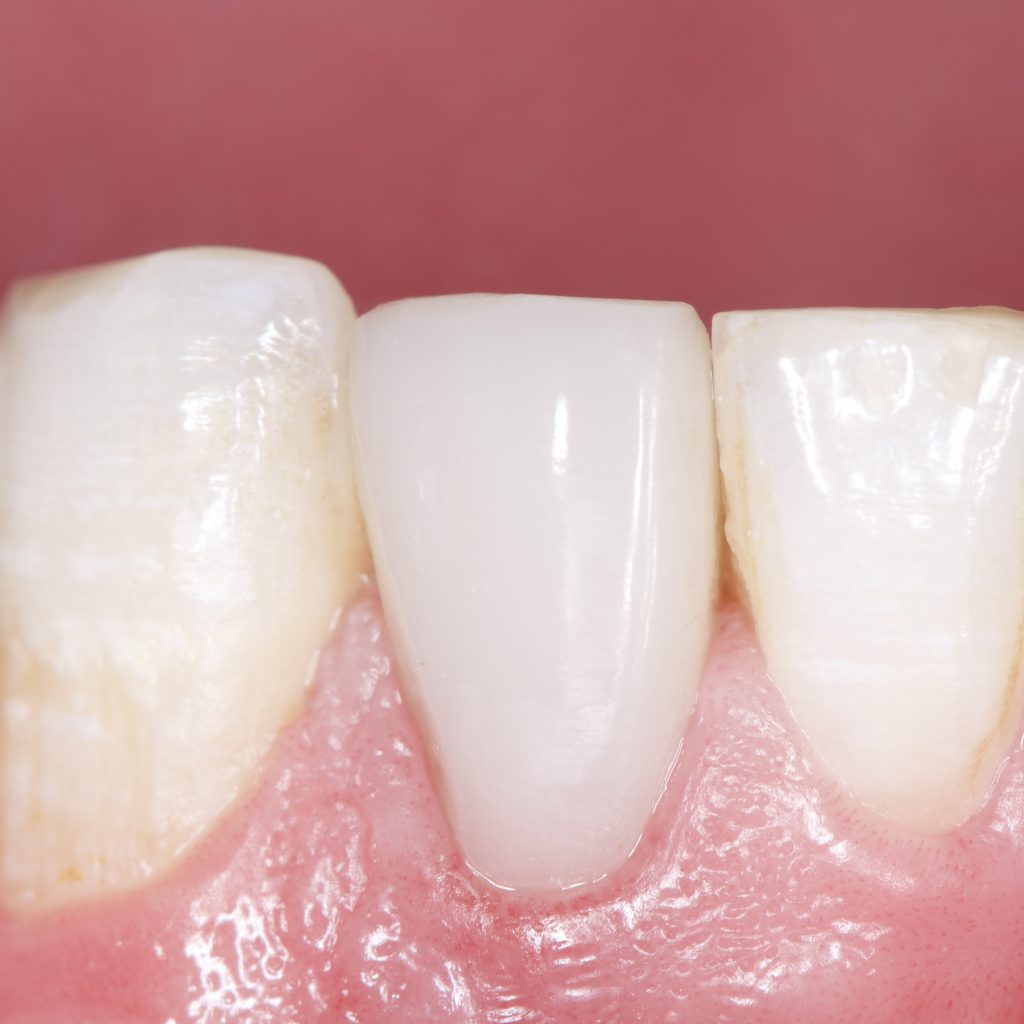

1 month Follow up